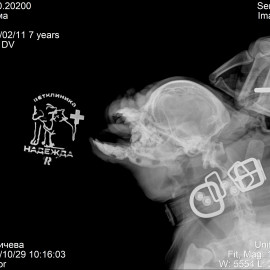

В другой клинике был поставлен диагноз: перелом тела нижней челюсти правой и левой стороны. Была проведена операция: остеосинтез нижней челюсти.

Снимок 3-4 после операции.